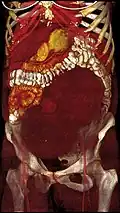

Multiple uterine leiomyoma

Sub-serosal uterine fibroid

Multiple uterine leiomyoma with calcification

Fibroids are monoclonal tumors and approximately 40–50% show karyotypically detectable chromosomal abnormalities. When multiple fibroids are present they frequently have unrelated genetic defects. Specific mutations of the MED12 protein have been noted in 70 percent of fibroids.[30]